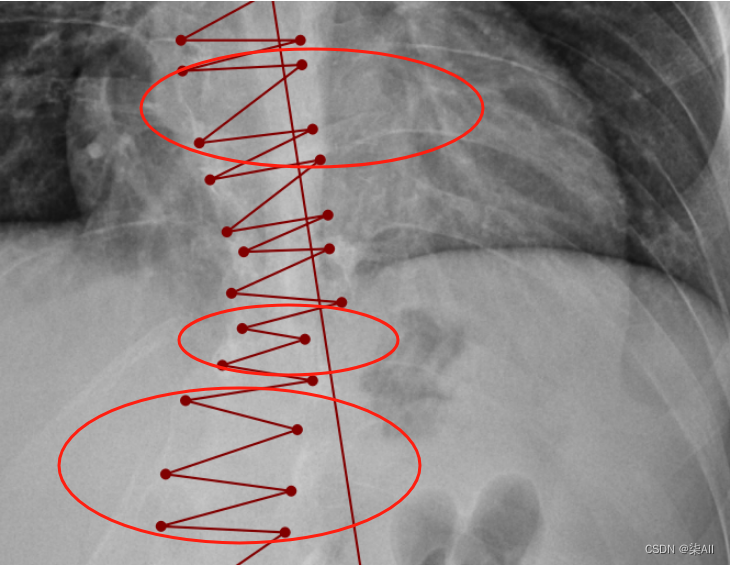

- (3)像这种椎骨不要变化太大,一般都是底下的椎骨大一些,往上逐渐减少,就因为看不清,所以得这样表

- (4)还是有很多问题的,这种计算cobb角肯定有问题,最后一个椎骨看不清,那画的线就与上一个椎骨平行,尽量平行标,要不然后面自动生成cobb角,误差很大,这样肯定不行,注意一下,认真一些,要不然得返修几次,不如好好弄,还节省时间

(3)像这种椎骨不要变化太大,一般都是底下的椎骨大一些,往上逐渐减少,就因为看不清,所以得这样表

还是有很多问题的,这种计算cobb角肯定有问题,最后一个椎骨看不清,那画的线就与上一个椎骨平行,尽量平行标,要不然后面自动生成cobb角,误差很大,这样肯定不行,注意一下,认真一些,要不然得返修几次,不如好好弄,还节省时间

###(5) 参考AASCE2019 GT图